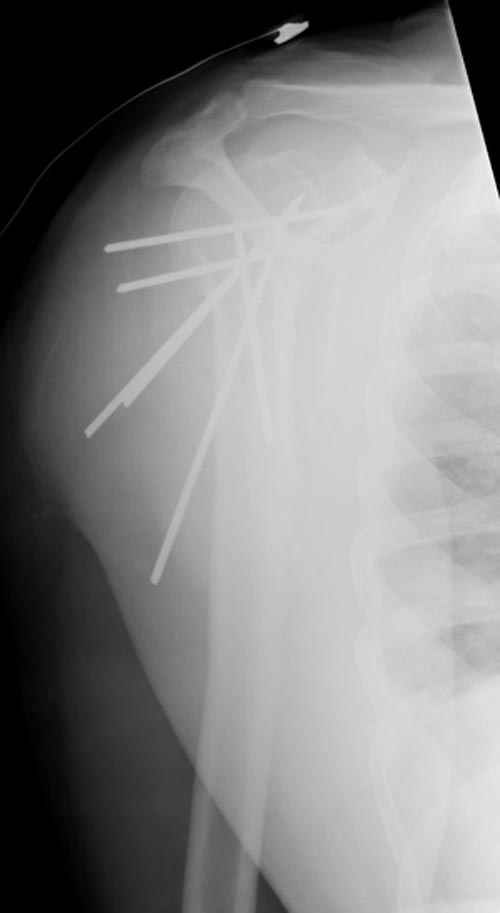

Клинические снимки - 3 недели после операции

с уважением М. Беренштейн

сделать закрытую репозицию с помощью ЭОПа совсем не сложно, после этого еще проще провести 3-6 спиц и получить красивую рентгенограмму. Есть только небольшая проблема это ROTATOR CUFF. Для плечевого сустава только костное восстановление не достаточно. для функции плечевого сустава нужны вращатели.

Давайте представим себе состояние манжетки вращателей после вывиха плеча, а еще и с отрывным переломом бугров. Головка может и прирастет, еесли не будет аваскулярного некроза, но хорошего функционального результата не ждите.

Висеть будет красиво. У людей физически активного периода жизни нужно открыть, восстановить костную анатомию и восстановить сухожильный аппарат.

В этом плане Locking plate очень хороша так как позволяет начать движения сразу после операции.